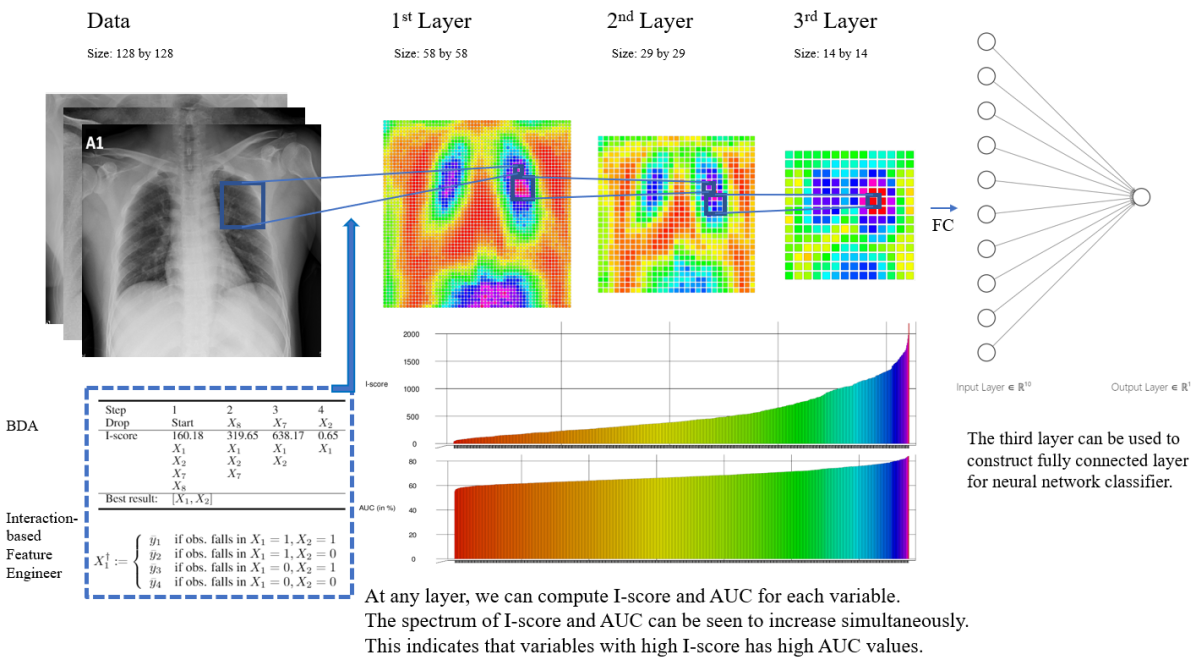

Chernoff, Lo, and Zheng (2009) [5] presents a general intensive approach, based on a method pioneered by Lo and Zheng (2002) [18] for detecting which, out of many potential explanatory variables, have an influence (impact) on a dependent variable . This paper presents an interaction-based feature selection methodology incorporating the notion of influence score, I-score, as a major technique to detect the higher-order interactions in complex and large-scale data set. Our work investigates the potential usage of I-score and a novel deep learning framework. The executive diagram can be seen in Figure 2 which outlines the road-map of the proposed methodology and the architecture of a novel Interaction-based Convolutional Neural Network (ICNN). This novel architecture takes full advantage of I-score and Backward Dropping Algorithm. In other words, it produces convolutional layers that are self-interpretable which provides explainable power to the features of image data at any convolutional layer if this design is implemented. In the following section, we discuss the contribution of our work and why the proposed method satisfies the three dimensions defined in §1. With all three dimensions satisfied (, , and ), the proposed design of an Interaction-based Convolutional Neural Network (ICNN) is the ideal candidate to address XAI problems.

The key novelty of our proposed approach (see Executive Design in Figure 2) rests on the collection of features identified by I-score. Based on the contributions described above, the proposed method is model-free and hence checks the first condition . It describes a quantifiable measure of how much a combination of explanatory variables impact the outcome variable which allows statisticians to make comparisons and screen for influential features. This phenomenon checks the second dimension . In addition, the statistics, I-score, provides a measurement for explanatory variables that is directly associated with the predictivity that the explanatory variables have on outcome variable which satisfies the third condition . With all three dimensions (, , and ) satisfied, the design of the proposed architecture presents an Interaction-based Convolutional Neural Network (ICNN) that is innately interpretable and explainable. It extracts influential information from the image data and generates explanatory features that directly associate with the predictivity of the data. Because all three dimensions are met, the proposed design of CNN is interpretable and it serves as the touchstone in the field of XAI. For more detailed discussion, please see Appendix 5.1.

The illustration of the proposed Interaction-based Convolutional Nerual Network (ICNN) is presented in Figure 2. This executive diagram walks reader through a step-by-step procedure how the proposed network architecture is designed and why it satisfies the three dimensions (, , and ) in the definition of interpretability and hence can be the benchmark address XAI problems.

Proposed Architecture. The executive diagram for the proposed architecture is presented in Figure 2. First, the architecture starts with image data that consists of X-ray pictures sized 128 by 128 (see detailed discussion of COVID-19 data set in §4). The architecture proposes using a rolling window with size 2 by 2 (we use a 2 by 2 window for simplicity and larger sizes can be applicable as well in practice depending on the data). Since the window size is 2 by 2, this means there would be four variables every time the window rests on a certain location of the image. Within this subset of variables, we execute the proposed method of Backward Dropping Algorithm (BDA). This procedure finely selects a subset of variables that is highly predictive by omitting the noisy variables in this small neighborhood on the image. Next, the selected variables (which can be any subset of the original four) go through a proposed procedure called Interaction-based Feature Engineer (see 4 for definition). The procedure of BDA is illustrated in the bottom left corner of the Figure 2 (we use a 2 by 2 window for demonstration purpose). In addition, we set the starting point to be 12 and this means we start from the pixel at the 12th row and the 12th column. From data (size of 128 by 128) to the 1st layer (58 by 58), this procedure gives us a new feature matrix with size on both edges which means the new feature matrix has 58 by 58 variables (the formula is presented in equation 8). This feature matrix constitutes the first Interaction-based Convolutional Layer. We can then use the same methodology to construct the second and the third Interaction-based Convolutional Layer. The third Interaction-based Convolutional Layer can be used as input layer for a neural network classifier. Each layer we can compute the proposed measure I-score and the AUC value (see §4.4 for detailed discussion of AUC values) for each variable (assuming using this variable as a predictor when computing the AUC value). The paths of I-score and AUC values have parallel behavior and this can be seen in the color palette of the spectrum in Figure 2.

Why Proposed I-score Satisfies XAI Dimensions. The design of the proposed architecture in Figure 2 mainly focuses on using I-score and Backward Dropping Algorithm to extract and engineer features from the original images. The proposed measure I-score is non-parametric (see §3.1 for definition of this measure). This means the impact of how explanatory variables affect response variable measured by I-score does not rely on the knowledge of the correct specification of the underlying model. In other words, the computation of I-score does not rely on any model fitting procedure. This characteristic satisfies the first dimension, , defined in §1 about interpretable measures.

Next, the proposed architecture is transparent at disclosing to its human users what location of the image is important at making decisions about prediction and what location is noisy. In every Interaction-based Convolutional Layer, we can compute the proposed measure I-score for any single variable. We can also compute I-score and finely select predictive variables from any combination of variables. The larger the I-score values the more important the variables are at making predictions. With simple visualization presented in Figure 2, we are able to use a spectrum of different colors to illustrate this phenomenon. We can code high I-score values to be one side of the color spectrum and the low I-score values to be the opposite side. The areas that are informative have high I-score values and have very different color than areas that are noisy. This characteristics of I-score allows the statistician to make comparisons and variable selection assessment. Therefore, it satisfies the second dimension, , defined in §1.

Third, the proposed architecture has a direct association with the predictivity (see equation[2] of [17]) of a variable set. This means that the important features screened by I-score provide the statistician how much impact this variable set has on the response variable. In addition, it is beneficial to be able to compute I-score for any variable in any Interaction-based Convolution Layer which implies that the association with the predictivity is well stated each step in the architecture. This can be visualized using the AUC values (see §4.4 for detailed discussion of AUC values) that are coded onto the same spectrum location of I-score values. Moreover, we observe the path of I-score and AUC values to have parallel behavior. This implies that the values of I-score and AUC move up and down together which means for each variable with high I-score measure would definitely have high AUC values and vice versa. This interesting yet powerful phenomenon allows this architecture to satisfy the third dimension, , stated in the definition of an interpretable measure which is novel in the literature.

This executive diagram summarizes the key components of the proposed methods of this paper. We start with the COVID-19 Image Data. With a small rolling window defined, we execute the Backward Dropping Algorithm to select the important features within this window. For example, the rolling window may cover 4 variables, and BDA could select as a variable module. Then we can construct a new variable using the technique of Interaction-based Feature Engineer (see the construction of in equation 4 to appreciate this new design). In other words, using the selected variables and , we construct . The procedure of BDA is illustrated in the bottom left corner of the figure (we use a 2 by 2 window for simplicity). We set the starting point to be 12 (i.e. start from the pixel at the 12th row and the 12th column). From data (size of 128 by 128) to the 1st layer (58 by 58), this gives us a new dimension that is computed by (see equation 8). We can repeat the process in the 2nd Layer and the 3rd Layer. After the 3rd Layer, we shrink the dimension to 14 by 14 (which gives us 196 new variable modules, i.e. the new ’s). We fully connect these 196 variable modules with the 10 neurons in the hidden layer (in practice the number of hidden layer and the number neurons are tuning parameters). This novel design is fundamentally different than the conventional practice of using pre-trained filters, because it proposes to use an explainable measure I-score to extract and build information directly from images in the training data. For each local variable (in the data it is referring to pixels and in the layers it is referred as variables), we compute the I-score values and also the AUC (see §4.4 for detailed discussion of AUC values) for that variable (using this variable as a predictor alone). We observe that the I-score value fully represents the predictivity of each local variable which can be confirmed by the variable’s AUC value. The color spectrum of both I-score and AUC are presented in the bottom part of the diagram. We observe I-score values exhibiting paralleled behavior with AUC values. This means the variables with high I-score values have high AUC values which indicates strong predictive power for the information in that location. This design heavily rely on I-score and has an architecture that is interpretable at each location of the image at each convolutional layer. More importantly, the proposed design satisfies all three dimensions (, , and in §1 Introduction) of the definition of interpretability and explainability.